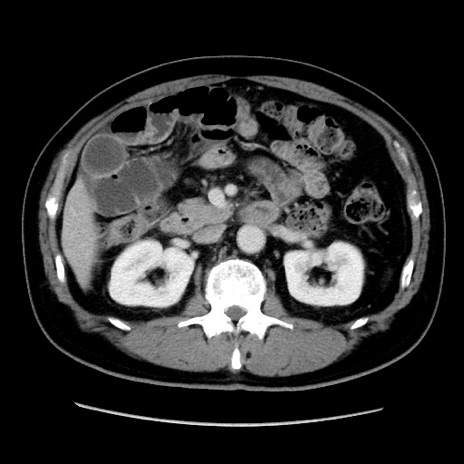

症例16(横断像)

【症例】 70歳代男性

【主訴】 腹痛、嘔吐

【現病歴】 約1ヶ月前より間欠的に腹痛と嘔吐あり、当院消化器内科を受診したところCTで多発する肝臓のLDAを指摘され、精査中であった。以降は消化器症状は安定していたが、2日前より嘔気と腹痛があり、同日より排便・排ガスが消失した。改善認めず、 本日、救急外来を受診した。

【身体所見】意識清明・会話良好、BT 36.3℃、BP 127/80mmHg、 P 80bpm、腹部:膨満あり、平坦・軟、上腹部正中および下腹部正中に圧痛あり、反跳痛なし、筋性防御なし。

【データ】WBC 7200、CRP 0.77